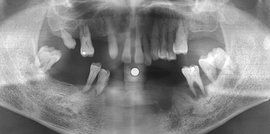

牙槽骨吸收的方式和程度,可通過X線片來觀察。正常情況下,牙槽嵴頂到釉牙骨質界的距離約為1~2mm,若超過2mm則可視為牙槽骨吸收。牙周炎的骨吸收最初表現為牙槽嵴頂的硬古板消失,或嵴頂模糊呈蟲蝕狀。